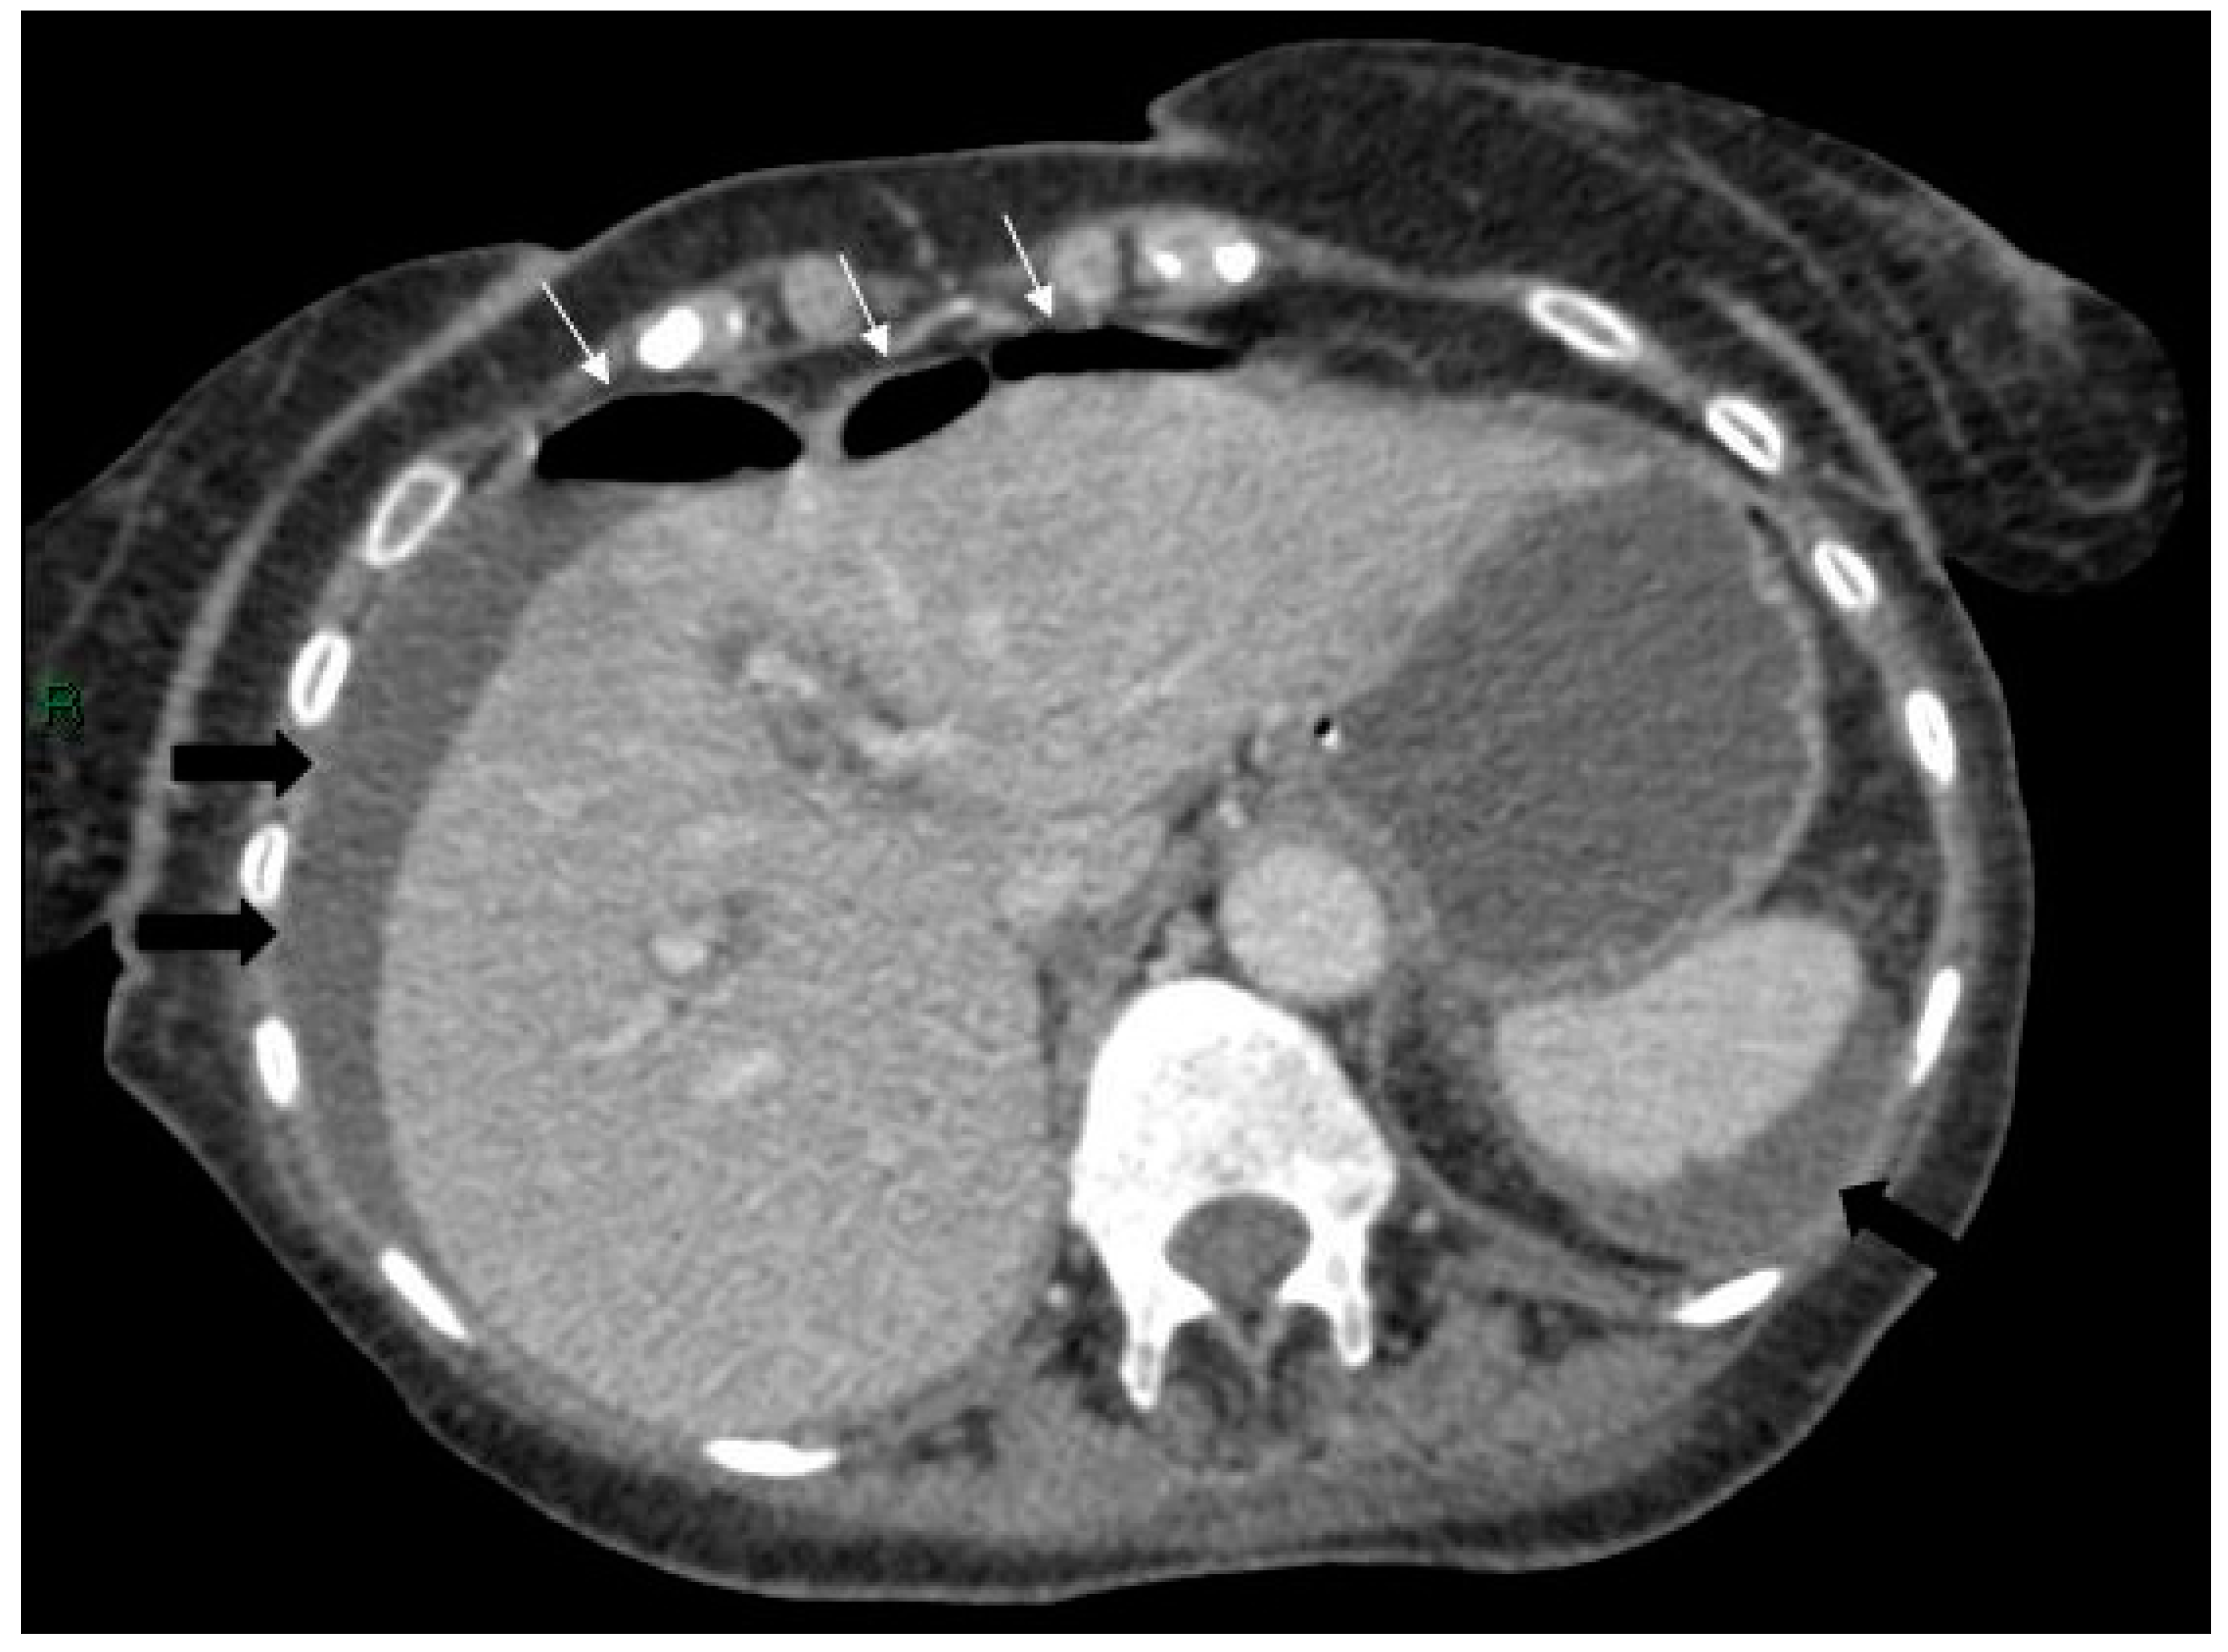

Figure 3.

Axial CT scan of the abdomen showing free air anterior to the liver (white arrows) and free fluid around the liver and spleen (black arrows).